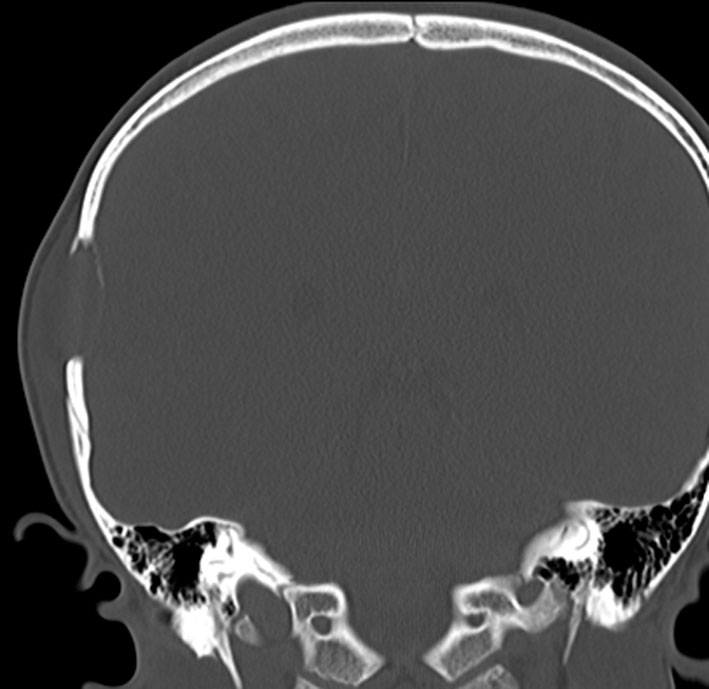

CTで典型的な頭蓋骨の打ち抜き像 punched out lesion が左頭頂骨にあります。これだけでLCHと診断がつくような画像です。

- 頭蓋骨が丸く抜けるように破壊されるのでpunched out lesionと表現されます

9歳の男の子です。右側頭部が腫れてきたのに気づきました。頭蓋骨のいびつな破壊像があります。